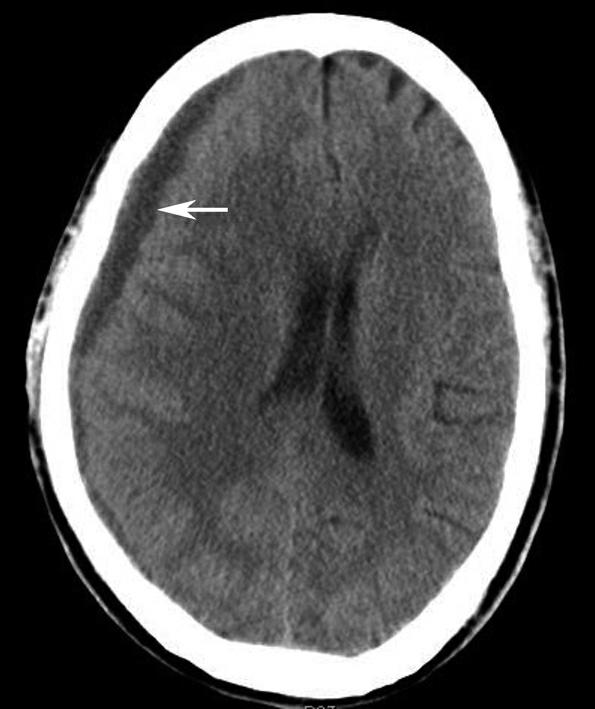

蝶鞍两侧为海绵窦,其内包含颈内动脉及第Ⅲ~Ⅵ对脑神经。海绵窦的密度升高或体积增大常提示病变存在。海绵窦外侧为颞叶,两者之间隔以海绵窦外侧壁。鞍背后方为桥前池及其后方的脑桥,桥前池内可见基底动脉断面,呈圆形稍高密度影。层面中部两侧为颞骨乳突部,其内气化的骨性腔隙为乳突气房。脑桥后方为第四脑室,呈半圆形或新月形,小脑半球的病变(如肿瘤、炎症、出血等)常压迫第四脑室,导致其变形甚至闭塞(图1-2-13)。两侧小脑半球间为小脑蚓部。小脑半球与颞骨乳突部间可见乙状窦。小脑蚓部后方为直窦与上矢状窦汇入窦汇处,窦汇两侧为横窦。静脉窦血栓时可见上述静脉窦增宽、密度明显升高(图1-2-14)。

图1-2-13 第四脑室变形(小脑转移瘤)

A.第四脑室受压变形右移(白箭),提示左侧小脑半球病变;B.左侧小脑半球环形强化结节(黑箭),为瘤体,其周围伴有低密度水肿区